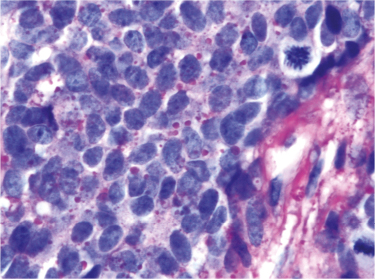

Fig 3

Figure 3. CD99 expression in ES/PNET. Immunohostochemistry of Ewing sarcoma/Primitive neuroectodermal tumor (ES/PNET) showing an intense membranous staining. It is imperative to emphasize that FLI1 immunohistochemistry is standard of care because of the non-specificity of the CD99 antigen. Thus, a positive CD99 staining result must be validated by a nuclear FLI1 immunohistochemical result, which is not demonstrated here. FLI1 is the surrogate marker for characteristic EWSR1-FLI1 translocation. A minority of ES/PNET disclose a translocation involving the EWSR1 gene and an alternative partner, most commonly the ERG gene, which is located on 21q12. (Avidin-Biotin Complex, anti-CD99 immunostaining, x400 original magnification).